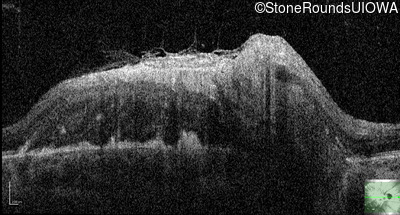

This 9 year old male was noted to have some crossing of his eyes at 2 months of age and the eye exam which followed identified a retinal lesion in the right eye. When he was six years old an epiretinal membrane was noted in his left eye. Two years later it was decided that it was a thin hamartoma in that eye as well. He underwent neuroimaging at age 7 which identified bilateral acoustic neuromas.